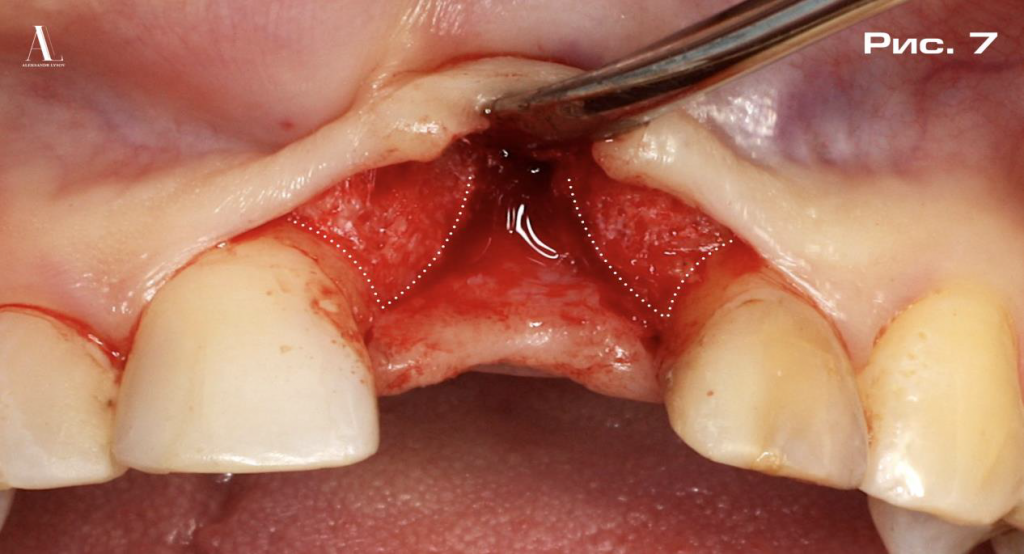

На рисунке 7 демонстрируется основная сложность данного клинического случая. Костный дефект достаточно выраженный, является сквозным, т.е. двухстеночным, но благодаря частичному сохранению костных пиков в области 1.1 и 2.2 зубов мы могли рассчитывать на успех лечения без применения многоэтапной костной пластики, а лишь с использованием каркасной аугментации мягких тканей.